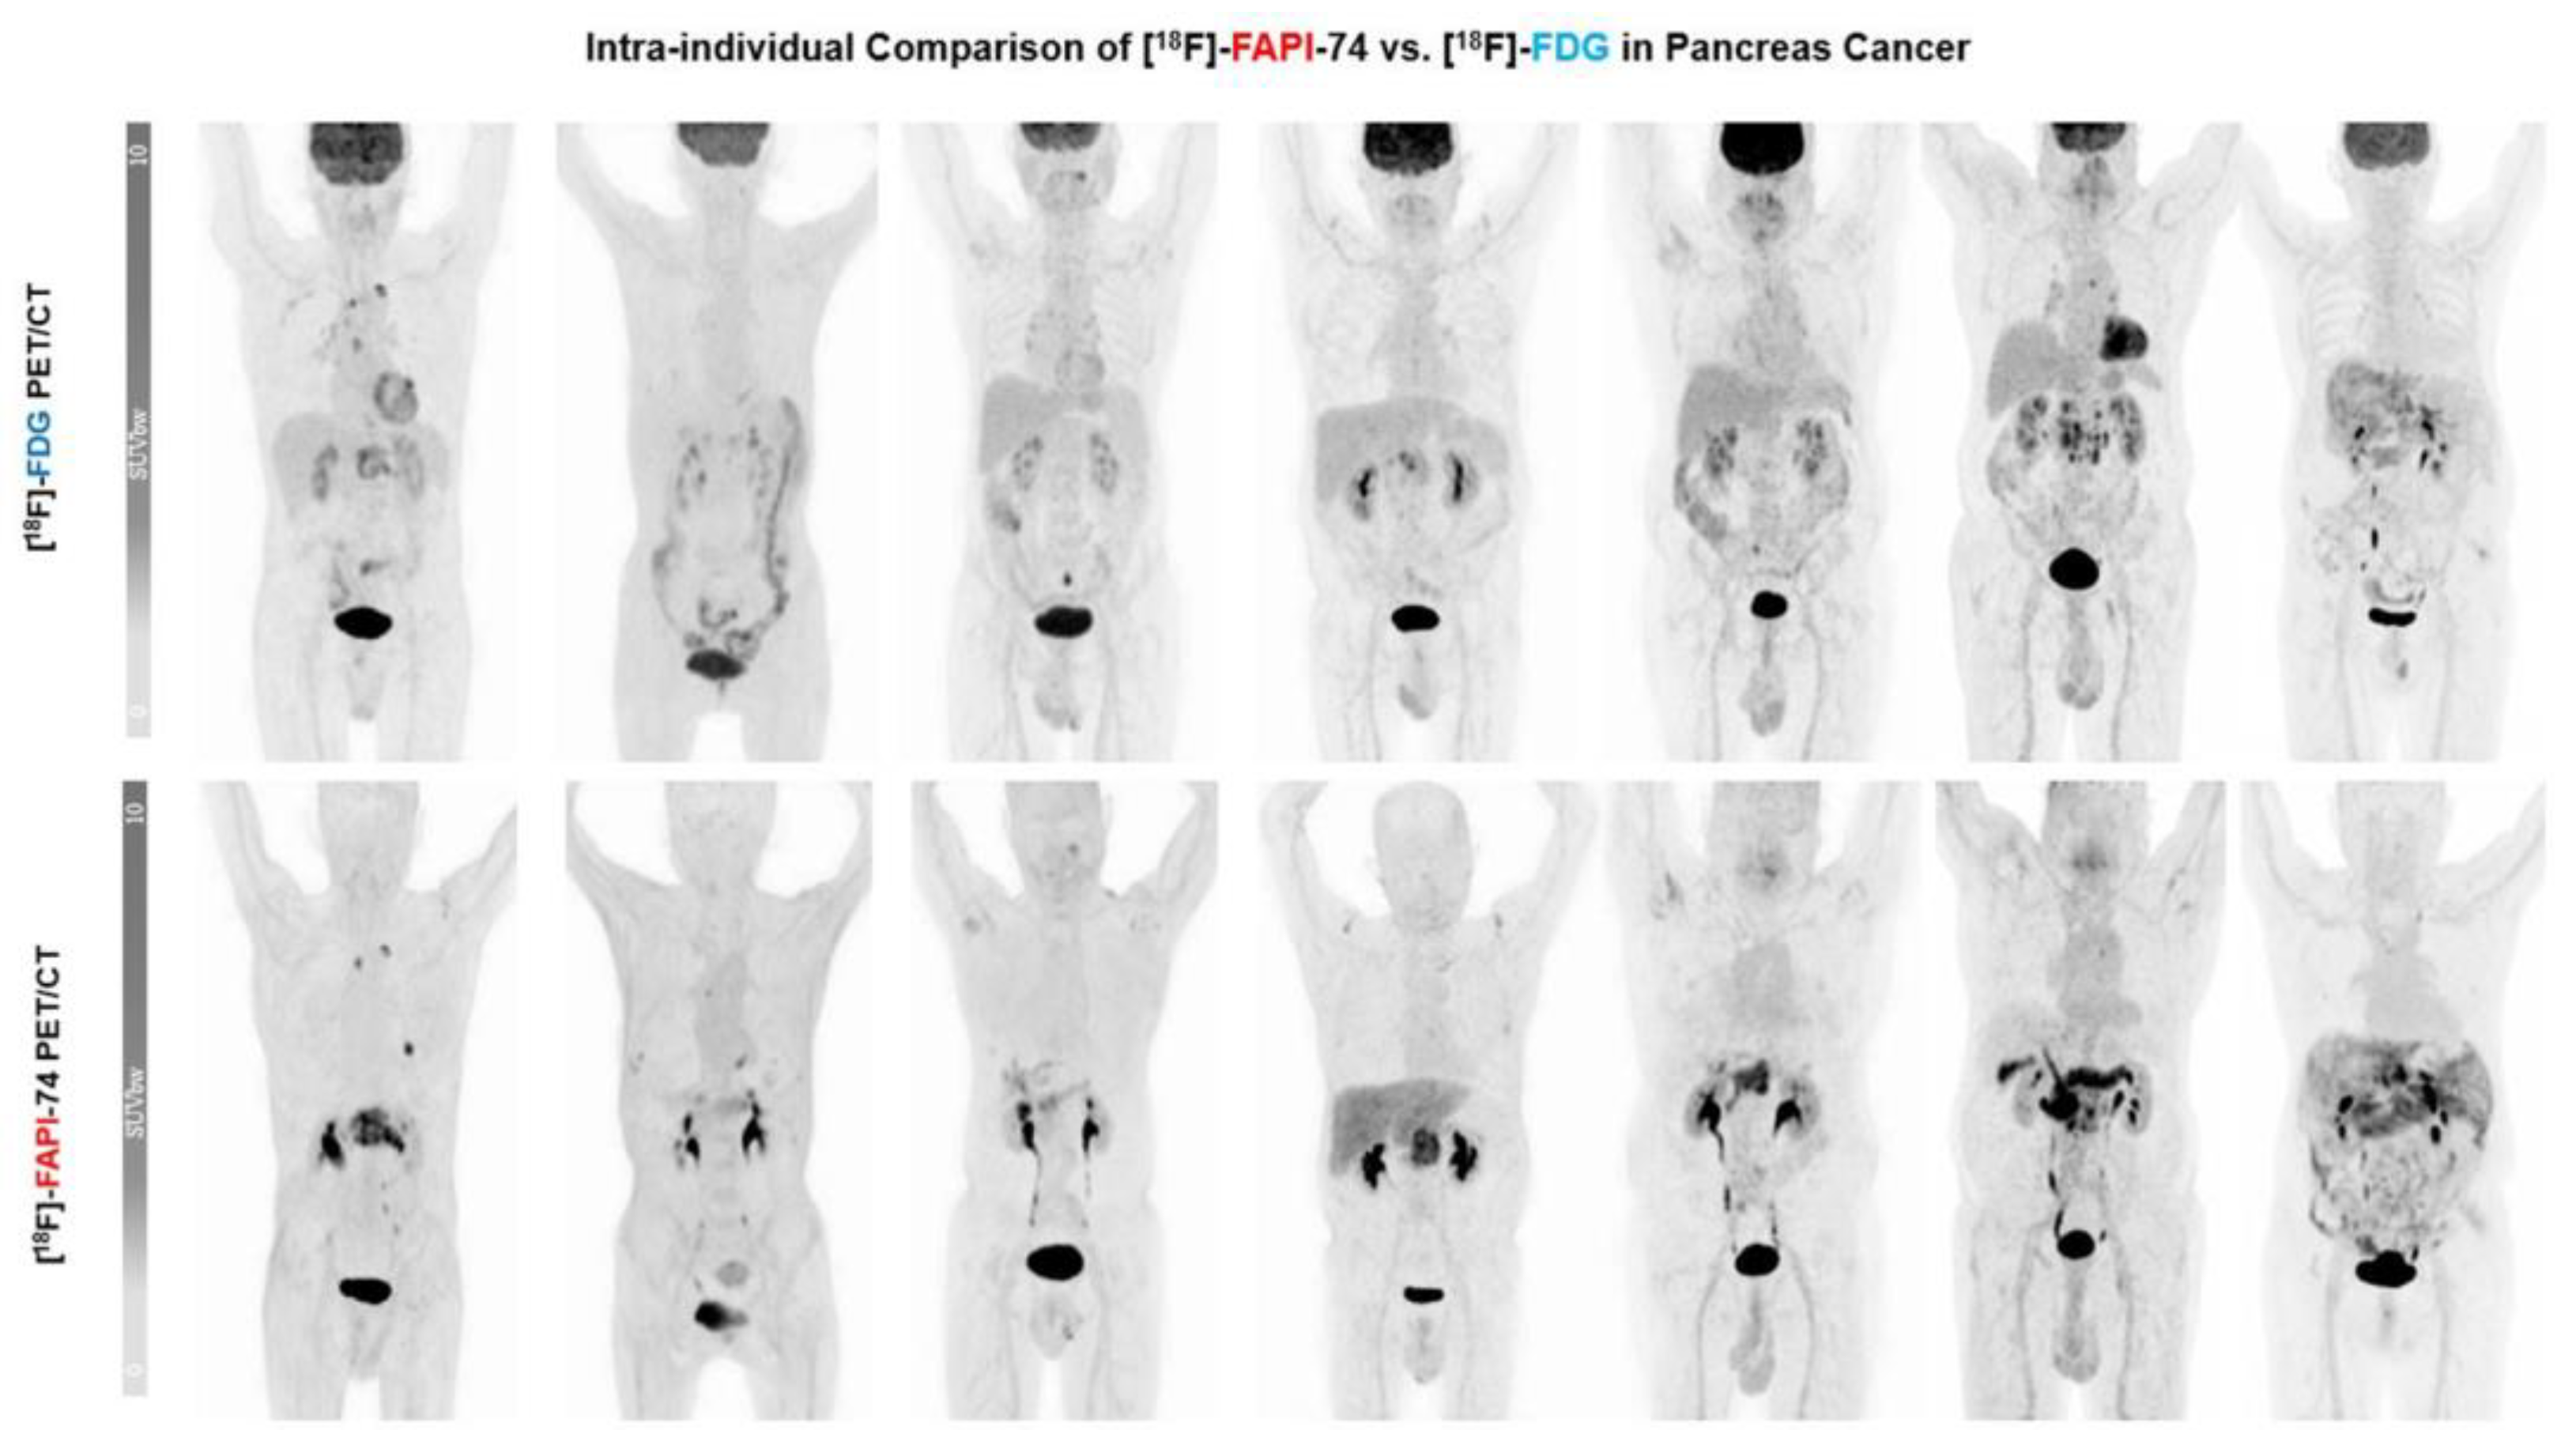

Head-to-Head Intra-Individual Comparison of Biodistribution and Tumor Uptake of [18F]FAPI-74 with [18F]FDG in Patients with PDAC: A Prospective Exploratory Study

- Giesel, F.L.; Kratochwil, C.; Schlittenhardt, J.; Dendl, K.; Eiber, M.; Staudinger, F.; Kessler, L.; Fendler, W.P.; Lindner, T.; Koerber, S.A.; et al. Head-to-head intra-individual comparison of biodistribution and tumor uptake of 68Ga-FAPI and 18F-FDG PET/CT in cancer patients. Eur. J. Nucl. Med. Mol. Imaging 2021, 48, 4377–4385. [Google Scholar] [CrossRef]